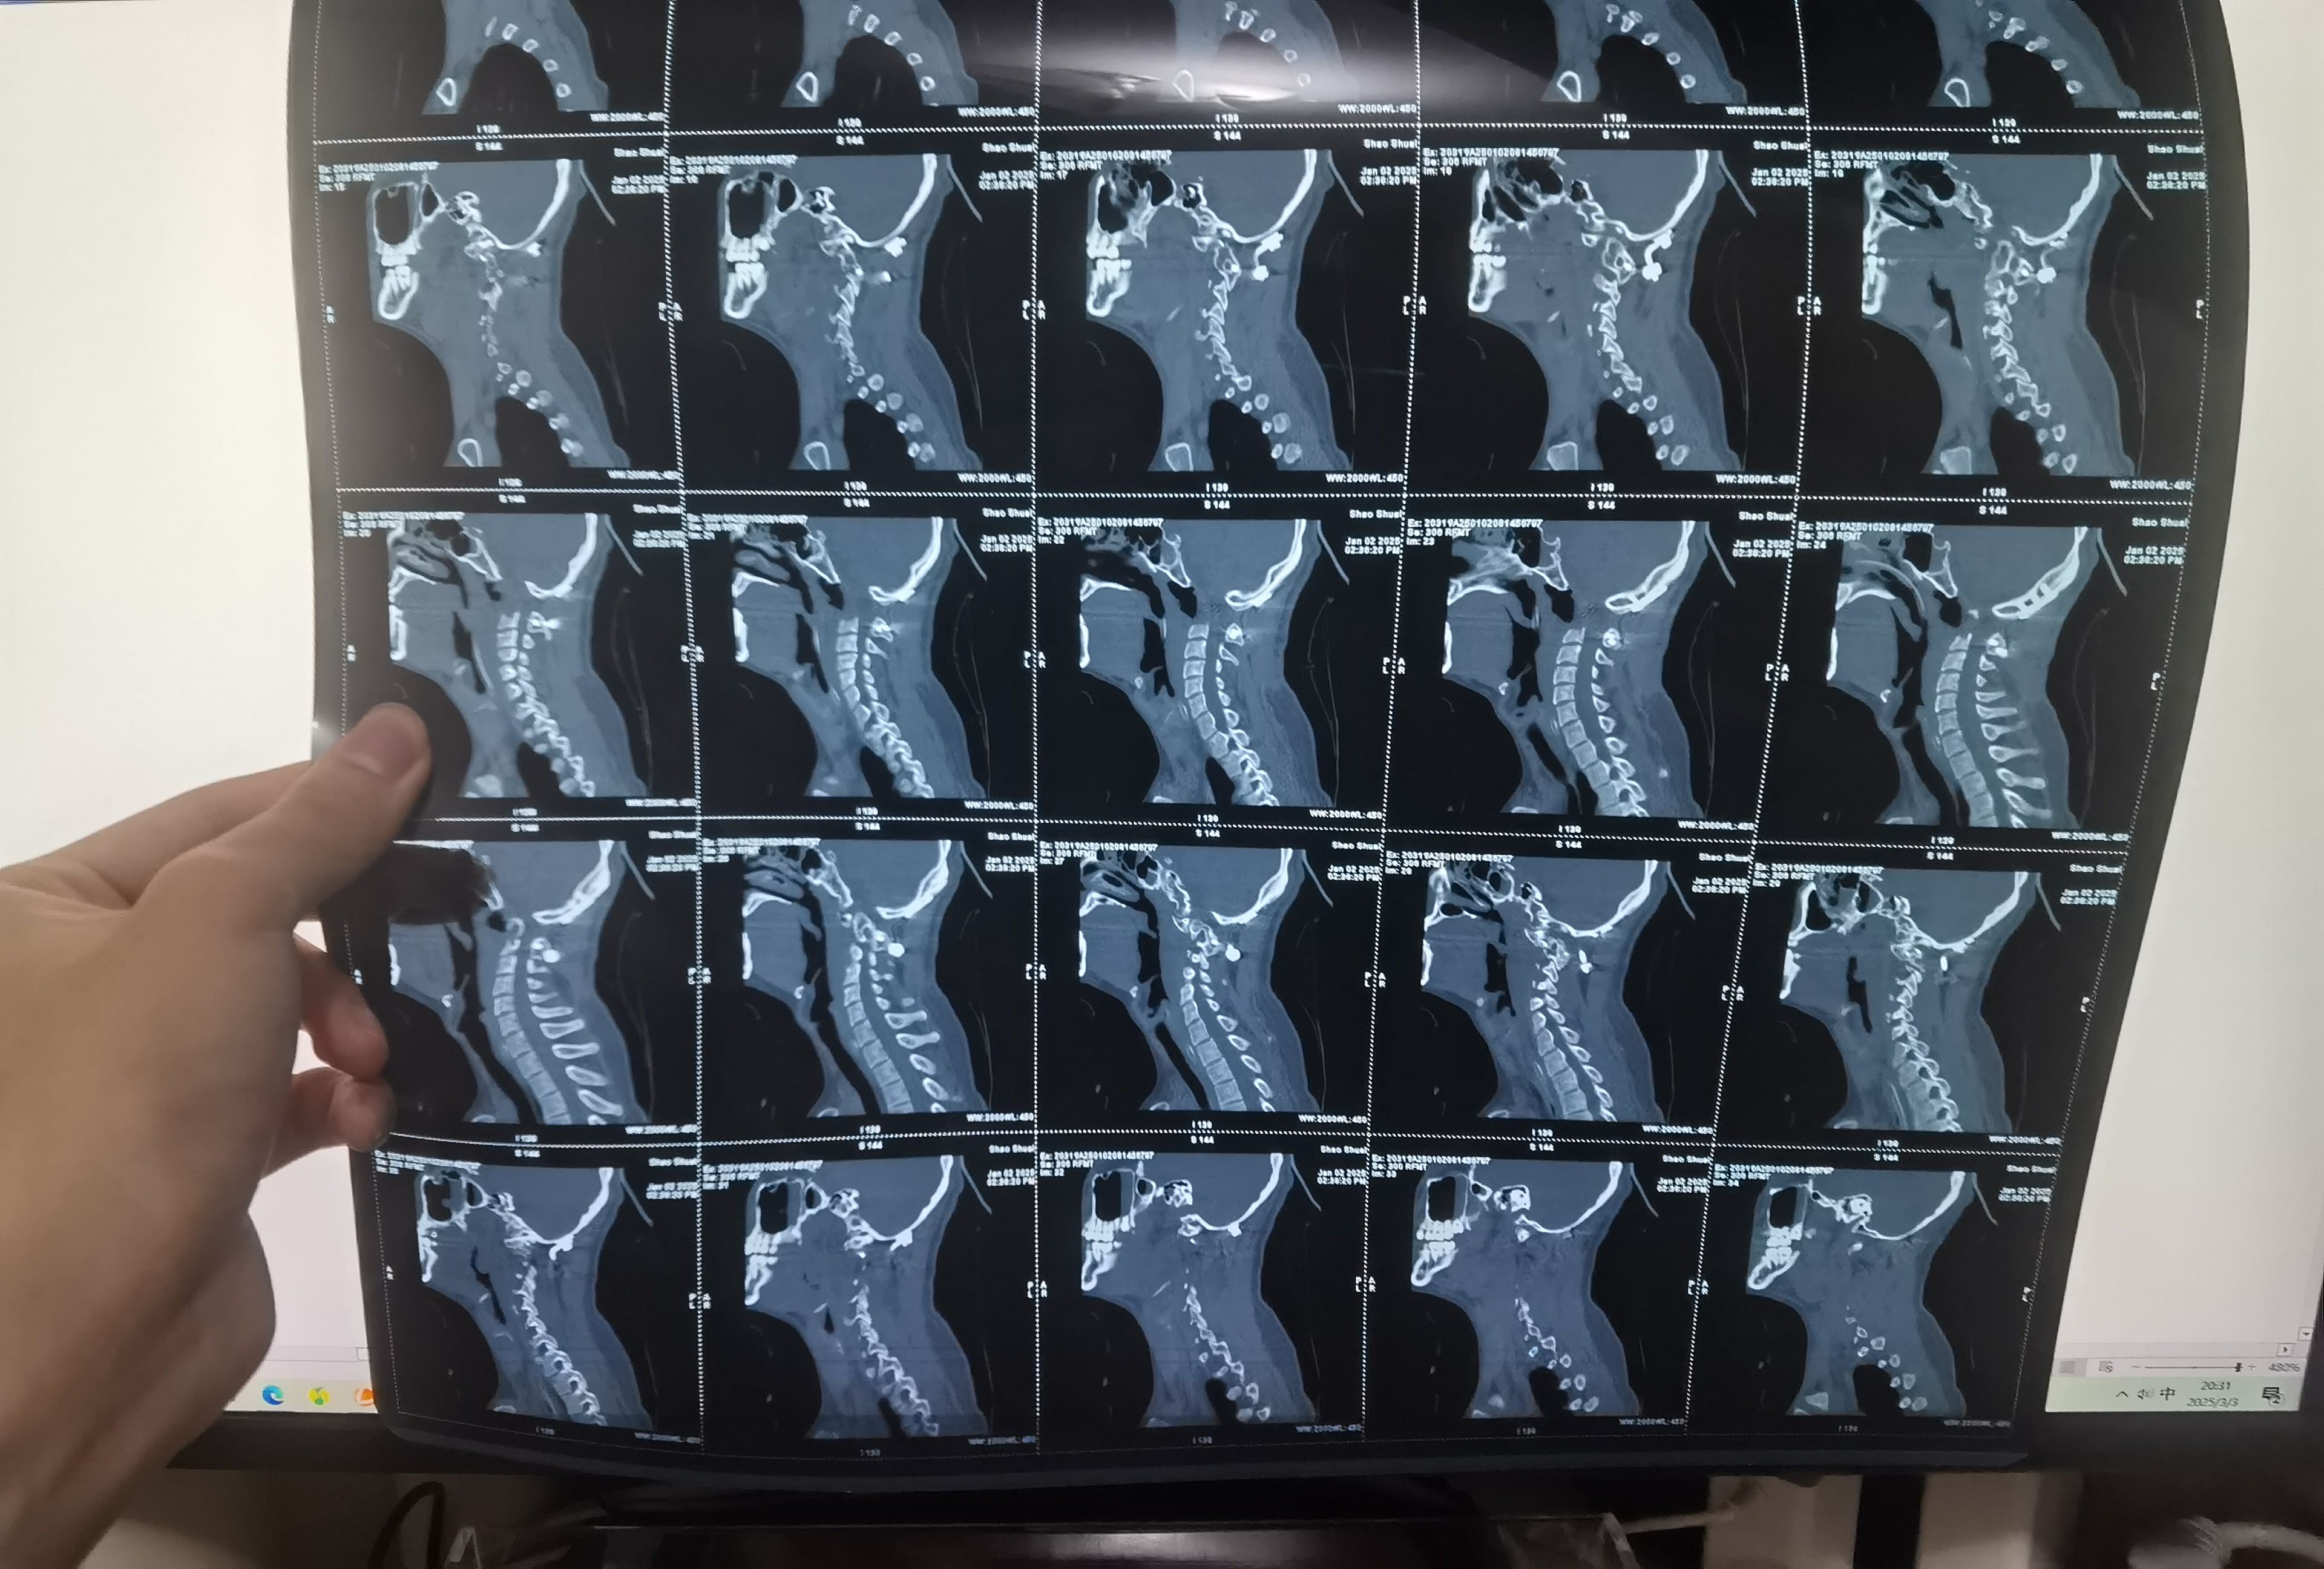

• 诊断:寰枢椎脱位

• 术后状况:术中放了融合器

• 清楚多久之后复位丢失。陈赞说是松解不到位导致的复位丢失。

• 日期:2024.12.31

• 医院:宣武医院

• 主刀:陈赞,段婉茹一助

• 术后状况:切除齿状突,效果良好

• 术后影像: